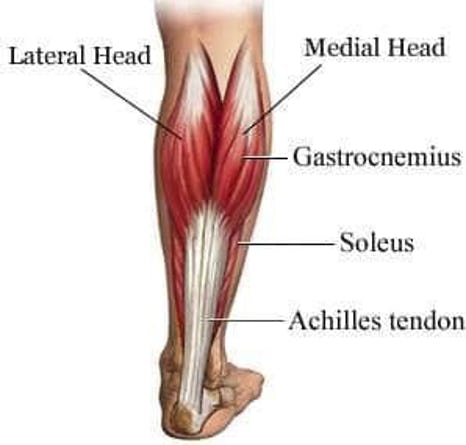

Your Achilles tendon has an important job. It is the strongest tendon in your body. It helps you point your foot down, rise up on your toes and push off when you walk or run. The Achilles tendon, also called the calcaneal tendon, is a band of fibrous tissue at the lower end of the calf. It connects the calf muscles to the heel bone. But this powerful tendon is also subject to painful injury.

Tendonitis, (also called tendinitis) is the inflammation of a tendon. The part of the tendon known as the watershed zone contains the weakest blood supply. Watershed zones are particularly vulnerable to inflammation and possibly rupture.

Insertional Achilles tendonitis affects the lower part of the heel, where the tendon is attached. Noninsertional Achilles tendonitis refers to fibers in the middle portion of the tendon which have broken down, swollen and thickened.